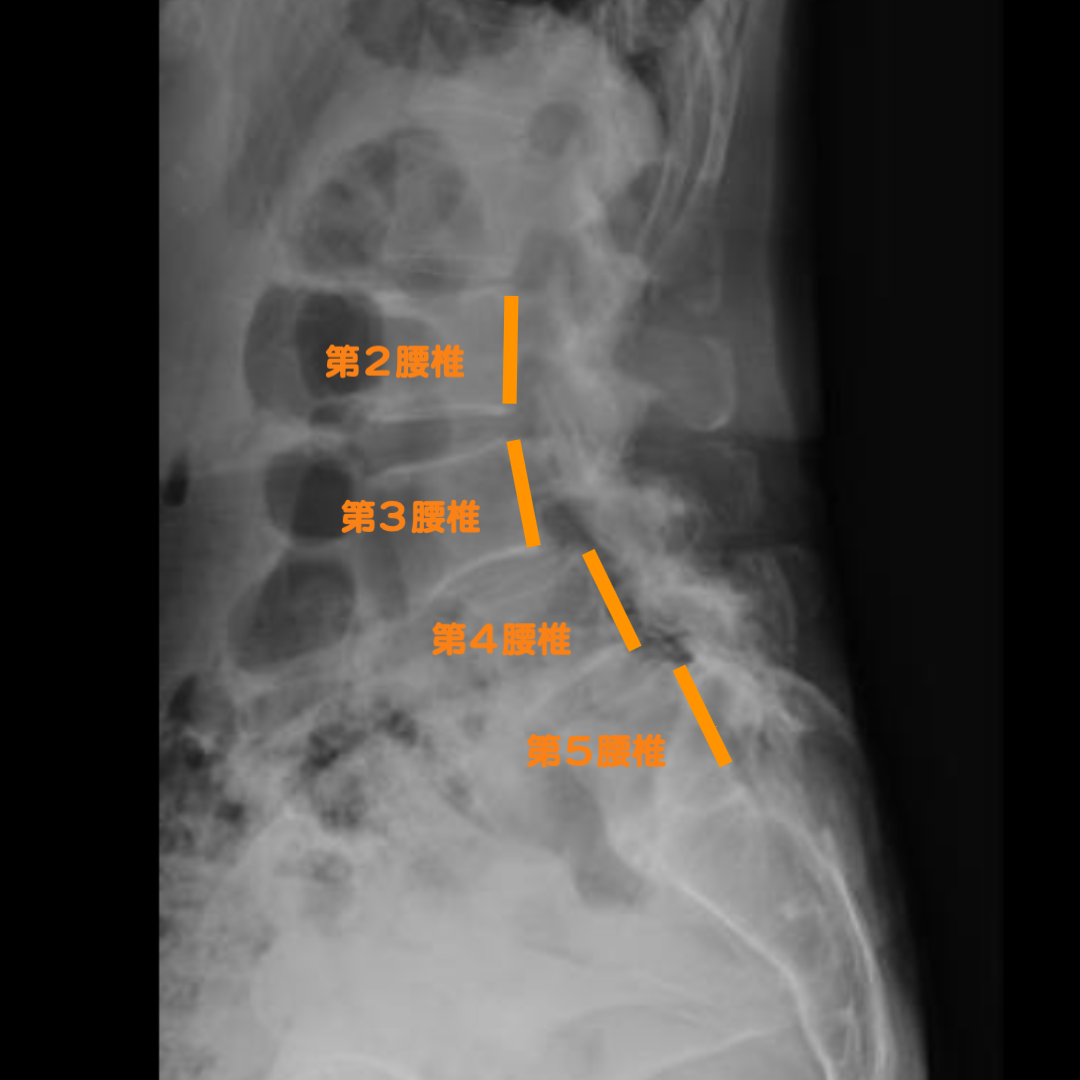

症例:滑り症による脊柱管狭窄症

歩いていると両太もも裏が痺れ、長く歩けない(間欠性跛行)。座って立ち上がると腰が起きないで屈んだ姿勢にしばらくなってしまう。第5腰椎に対しての第4腰椎が滑り、さらに第4腰椎に対して第3腰椎が滑っていました。